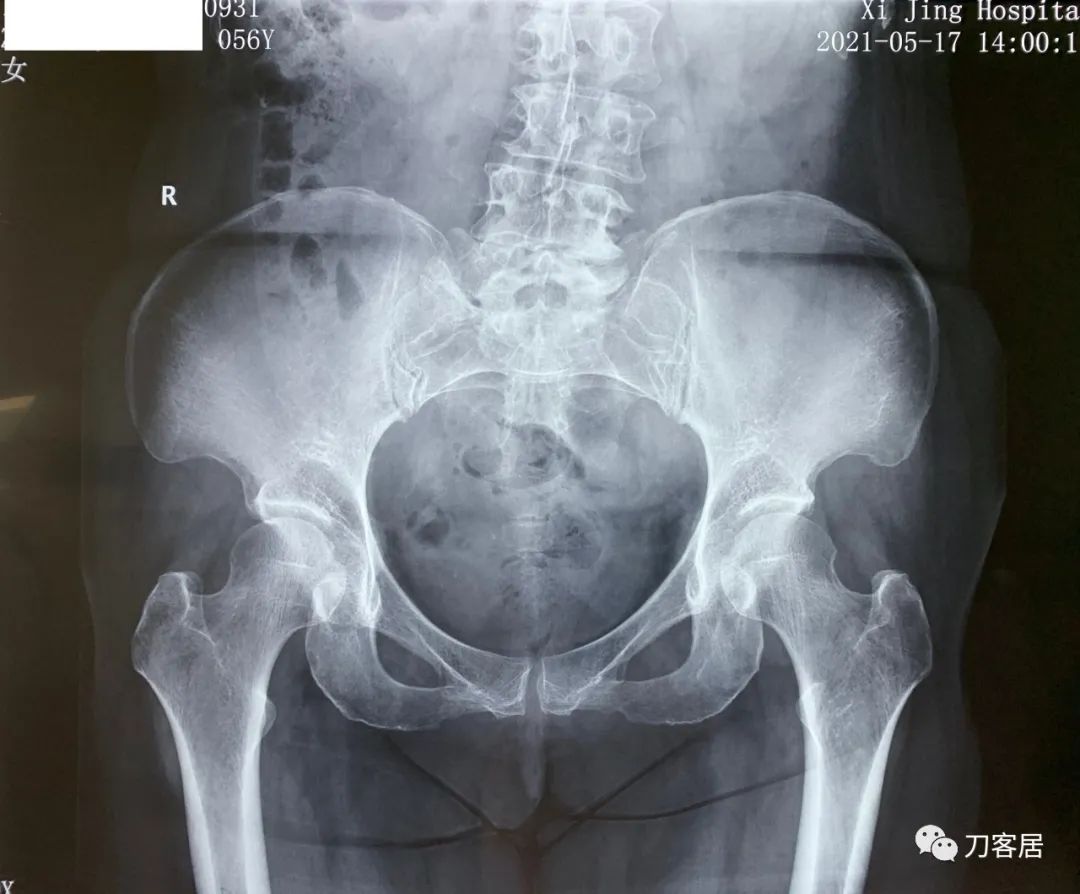

建议其查双光子骨密度,骨盆正位片以及腰椎间盘平扫。腰椎正侧位X线片以及动力位片,站立位脊柱全长正侧位X线片,以了解其是否有骨质疏松,并了解脊柱侧弯情况,腰椎局部X线表现情况和腰椎间盘突出和椎管狭窄情况。

从这个患者的影像资料分析,颈椎间盘突出问题不大,没有明确的上位神经元损伤表现,所以,不考虑颈椎和胸椎问题。腰椎侧弯畸形,但不严重。因为存在腰椎侧弯,使得腰椎MRI在扫描切面的时候,显示的椎间盘突出或椎管狭窄会有一定的误差,所以,又加做了经椎间盘的CT平扫,影像表现并不严重,综上,腰椎间盘突出,腰椎管狭窄,腰椎侧弯,不考虑手术治疗。同时,患者的主要痛苦是心理疾病,而不是器质性疾病,所以,以心身疾病治疗为主。虽然患者骨密度检查结果提示正常,但X线片显示骨质疏松,且其症状也与骨质疏松的症状有符合之处,比如静息痛,不能入睡,动作及姿势变换时痛加重等,所以,给予实验性抗骨质疏松治疗,以观疗效。